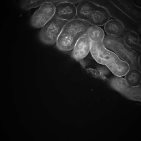

Our proposed method uses this inhomogeneity correction technique as a preprocessing step for both training and inference. Examples of original and inhomogeneity corrected images are shown in Figure 3a and Figure 3b, respectively.

The performance of our proposed method was tested on two different datasets:111 and were provided by Malgorzata Kamocka of the Indiana Center for Biological Microscopy. and . is comprised of grayscale images, each of size pixels, whereas consists of grayscale images, each of size pixels. We selected five different images from and generated corresponding manually annotated groundtruth images to train model . Our deep learning architecture was implemented in Torch [31] using a fixed learning rate and a momentum of . As indicated, pairs of images were generated by the elastic deformation, rotations, and flips using these five pairs of images. Note that each training data was used as a batch so that iterations were performed per epoch. We used epochs for training our proposed network. In addition, was used for the removal of small objects. The performance of the proposed method was evaluated using manually annotated groundtruth images () at different depths in that were never used during the training stage. For visual evaluation and comparison segmentation results of in using various techniques are presented in Figure 3.

The first row in Figure 3 displays an original microscopy image (), its inhomogeneity corrected version (), and manually delineated groundtruth (), respectively. For brevity we have omitted the superscript in the notation. The second row shows segmentation results of various 3D methods such as 3D region-based active contours [10] (3Dac), 3D active contours with inhomogeneity correction [11] (3DacIC), and 3D Squassh presented in [12] (3Dsquassh). Similarly, the third row portrays various segmentation methods particularly designed for tubular structure segmentation such as ellipse fitting method presented in [15] (Ellipse Fitting), the Jelly filling method in [20] (Jelly Filling), and tubule segmentation using steerable filter [21] (Steerable Filter). Finally, the last row shows segmentation results of our proposed CNN architecture without inhomogeneity correction [27] (2DCNN) and with inhomogeneity correction (2DCNNIC).

For visual evaluation we provide the segmentation results of the proposed method using two different datasets: and , sampled at different depths within the volumes. The first row shows original microscopy images , , and from and the second row displays the segmentation results corresponding to the first row. To better visualize the segmentation results, we highlighted individual tubules with different colors and overlaid them onto the original microscopy images. Similarly, the third row exhibits original microscopy images , , and from . Their corresponding segmentation results are shown in the fourth row. Note that the model which was trained on was used for during the inference stage. Although the shape, size, and orientation of tubular structures presented in are all different from , the proposed method can still successfully segment and identify individual tubules presented in as well as individual tubules in .